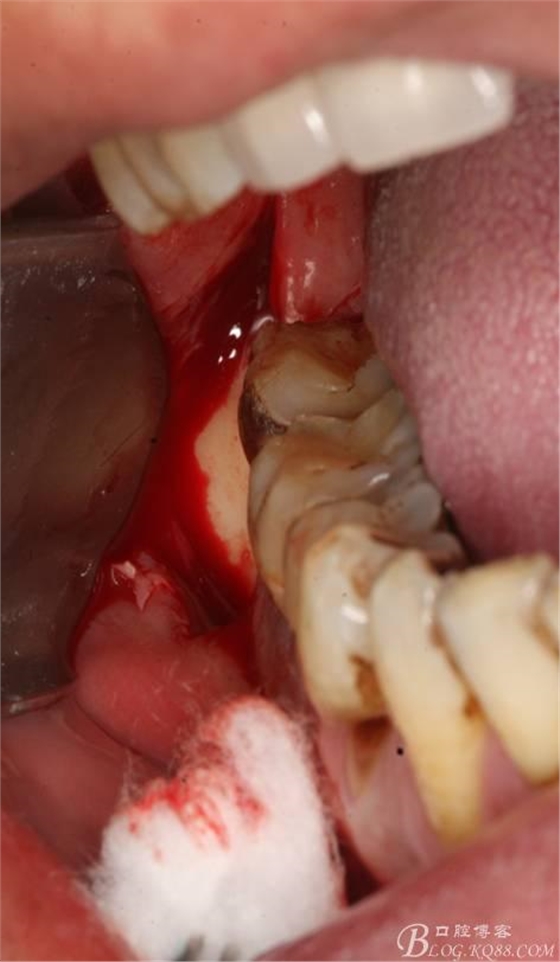

2.切開翻瓣

3.去骨、暴露48.